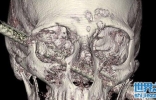

• 铁条刺穿从左脸颊到右眼球,工程师毫无痛感,医叹:幸运避开主动脉 ...

铁条刺穿从左脸颊到右眼球,工程师毫无痛感,医叹:幸运避开主动脉 ...

一位住在耶路撒冷、名为Rahman的建筑工程师,日前,他前往亲戚家协助帮忙盖房子,不幸的是,当他爬梯到二楼的高度时,意外踩空! 一个又尖又锐利的铁条直直刺穿他的头颅,从左下脸颊的部分直接刺穿至右眼窝,Rahma ...